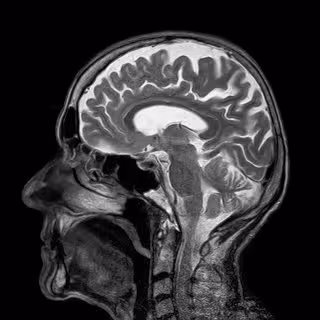

Se trata de una estructura clave en el procesamiento de las emociones que forma parte del sistema límbico. A diferencia de la corteza (parte externa que cubre los dos hemisferios y donde se localizan las funciones cognitivas superiores como el procesamiento visual o el lenguaje), la amígdala se sitúa en la parte interna del cerebro.

Sin embargo, esta ubicación, en la parte interna del cerebro, dificulta su estudio con las técnicas de habituales de neuroimagen. De hecho, para diagnosticar dolencias como la epilepsia, los neurocirujanos implantan electrodos en la amígdala.